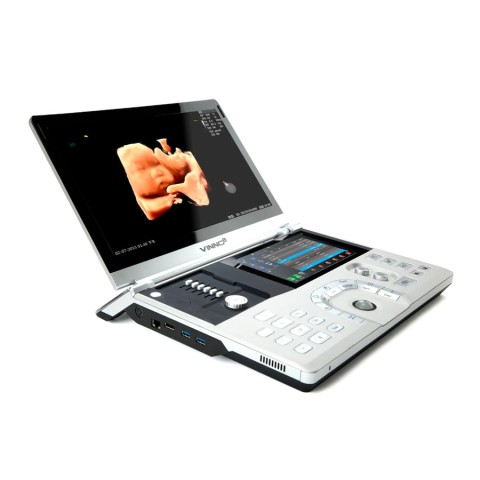

Портативный УЗИ аппарат VINNO 8

Портативный ультразвуковой сканер VINNO 8

Преимущества портативного УЗИ аппарата VINNO 8

- легкий вес и наличие командного 8-ми дюймового дисплея на панели управления

- ЖК монитор 15,6 дюймов, разрешение 1920х1080, угол наклона 30-150 град., угол обзора -178-178 град.

- Сенсорная панель управления 8 дюймов, разрешение 800х1280

- Электропитание – от сети 100-240 В, 50-60 Гц или от литий-ионного аккумулятора емкостью 5200 мАч, время зарядки 2,5 часа

- Потребляемая мощность – 170 ВА (макс.)

- Количество разъёмов для подключения датчиков – 1

- Количество моделей датчиков - 17

- Количество элементов в датчиках – 64-256

- Габаритные размеры - 387х340х72 мм

- Масса – 3,35 кг